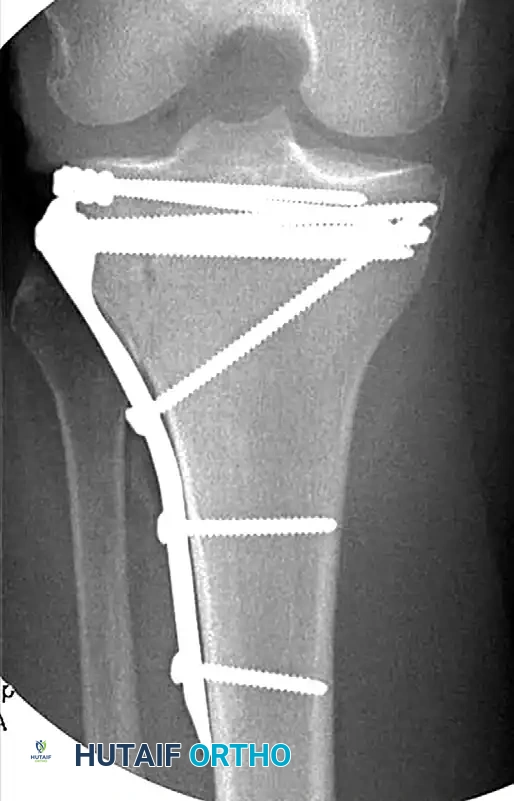

Open Reduction and Internal Fixation (ORIF)

Displaced fractures of the medial condyle (Schatzker IV) are high-energy, highly unstable injuries. They are best treated with open reduction and application of a medial buttress plate. Because the medial plateau bears approximately 60% of the knee's weight-bearing load, robust biomechanical support is mandatory.

For complex bicondylar fractures (Schatzker V and VI), traditional extensile exposures (e.g., Mercedes-Benz incisions or massive single midline incisions with extensive stripping) have historically resulted in catastrophic soft tissue complications, including flap necrosis and deep osteomyelitis.

Modern techniques emphasize minimally invasive plate osteosynthesis (MIPO) and dual plating through separate incisions. Mills and Nork demonstrated that dual plating can be safely achieved by utilizing an anterolateral incision combined with a posteromedial incision, leaving a wide, well-vascularized soft tissue bridge. Subperiosteal dissection is strictly limited to the fracture margins and the footprint of the plate. The use of small-fragment (3.5-mm) AO/ASIF T-plates has gained favor; their lower profile and increased malleability provide excellent buttressing of osteochondral fragments with significantly less soft tissue irritation than bulky 6.5-mm L-plates.